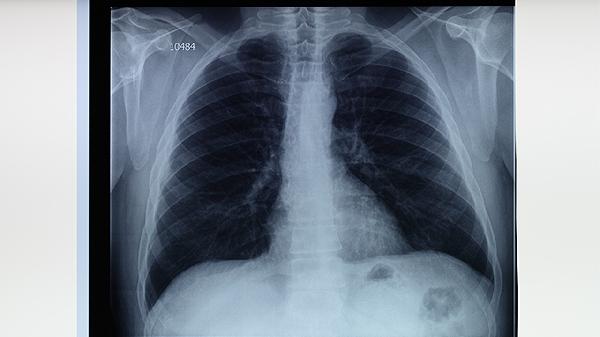

肺結(jié)核患者治療期間需保持規(guī)律作息,每日進(jìn)行散步等低強(qiáng)度運(yùn)動增強(qiáng)體質(zhì)。注意監(jiān)測體溫變化,記錄痰液性狀與咳血情況。居住環(huán)境應(yīng)保持干燥通風(fēng),避免去人群密集場所。定期復(fù)查胸部影像學(xué)與痰涂片檢查,評估治療效果。出現(xiàn)藥物不良反應(yīng)或癥狀加重時(shí)須立即就醫(yī)調(diào)整方案。完成全程治療后仍需隨訪觀察,預(yù)防復(fù)發(fā)。